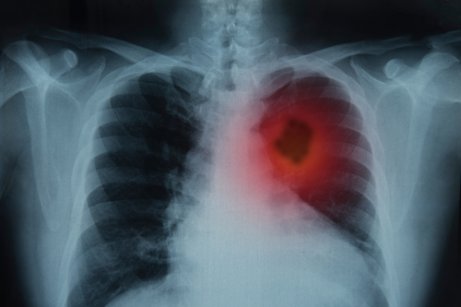

Har du dessa symptom och de håller i sig i mer än tre veckor är det viktigt att du uppsöker läkare för att göra en röntgenundersökning. Beroende på röntgenresultaten kan din läkare behöva din detaljerade medicinska journal och göra en fysisk kroppsundersökning kompletterade med laboratorietester.

- Radiologi och röntgen: Med denna metod kan läkaren ta bilder på områden inne i kroppen.